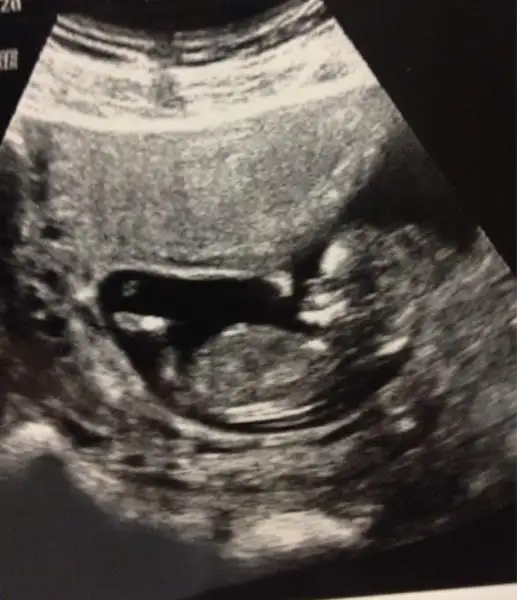

Herkese selamlar. Uzuun zamandır forumu takip ediyorum ama bu ilk mesajım. Kasım annesi olmam vesilesiyle yazmak istedim. Tahmini doğum tarihi 17 Kasım 2014 inşaallah. Herkesin bebeğini sağlıcakla kucağına almasını dilerim.